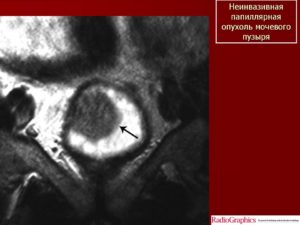

Неинвазивная папиллярная уротелиальная опухоль. Корональное Т2-взвешенное МР- изображение показывает тканевой интенсивности сигнала опухоль (стрелка),растущая в просвет мочевойго пузыря.

При бесконтрастном исследовании создается впечатление о сохранности прилежащих отделов гипоинтенсивной стенки мочевого пузыря.

Однако достоверно судить о степени глубины инвазии можно только по постконтрастным сканам.

При этом важно проведение именно динамического внутривенного контрастирования (в артериальную фазу происходит усиление только ткани опухоли, но еще не успевает произойти усиление интактной стенки мочевого пузыря). На представленном контрастном Т1-ВИ изображении (артериальная фаза) на фоне накопления КВ тканью опухоли, подслизистого слоя, видно отсутствие инвазии прилежащей стенки мочевого пузыря.